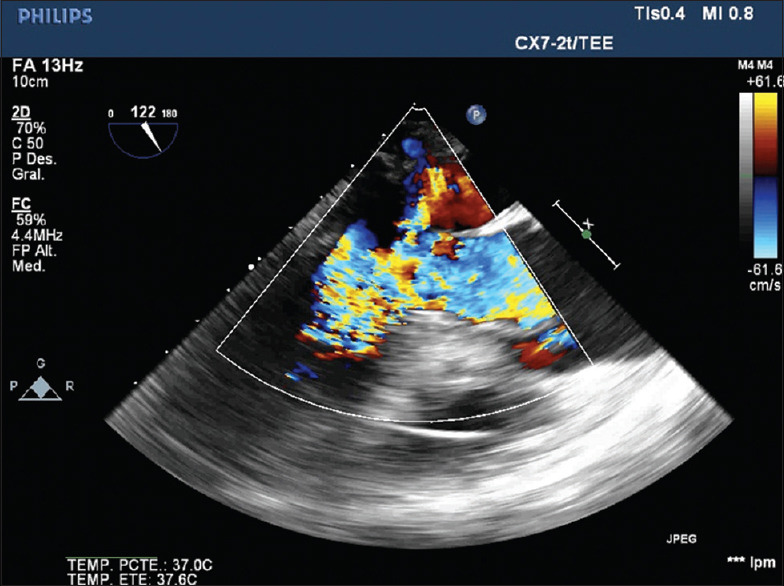

New Onset of Systolic Anterior Motion and Severe Mitral Regurgitation after Warm Ischemia in Donation after Circulatory Death Heart Transplantation.

Abstract: Donation after circulatory death is helping to expand the donor pool for heart transplantation. Nevertheless, these hearts are more susceptible to myocardial edema and decision of accepting the organ can be a challenge for the heart transplant team. Hemodynamic and echocardiographic criteria are used routinely, but there is still a lack of strong evidence that supports the decision-making in particular situations. That is why the authors found useful to analyze a case with a good outcome that could help accepting more organs in a situation of shortage.